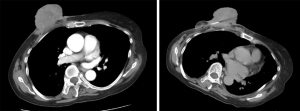

The total follow-up period for this patient was 4 months. She experienced oozing and a small amount of bleeding for around 1 month after Co-A, and the patient attended the wound care clinic regularly. Gradually, the tumor body was necrotic and detached (Figure 6). By 1 month after Co-A, there was no longer any bleeding, abscess, or exudate. At 4 months after Co-A, she was evaluated for efficacy through contrast-enhanced CT examination, suggesting that the tumor body had detached and the range of the mass was 8 cm × 2 cm. In the arterial phase, the CT value of the lesion area was 32–62 Hounsfield units (HU) (Figure 7). Her efficacy assessment was partial response. Nevertheless, it is worth noting that we performed an efficacy assessment based only on imaging data and did not perform a pathological review after the integrated treatments.